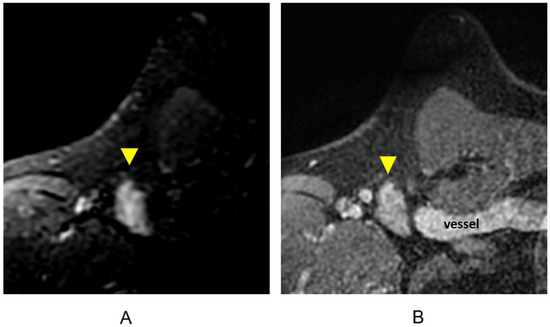

3.1.6. Evaluation of Internal Mammary Lymph Nodes (IMLNs)

- Behzadi, S.T.; Moser, R.; Kiesl, S.; Nano, J.; Peeken, J.C.; Fischer, J.C.; Fallenberg, E.M.; Huber, T.; Haller, B.; Klein, E.; et al. Tumor Contact With Internal Mammary Perforator Vessels as Risk Factor for Gross Internal Mammary Lymph Node Involvement in Patients With Breast Cancer. Int. J. Radiat. Oncol. Biol. Phys. 2024in press. [CrossRef] [PubMed]